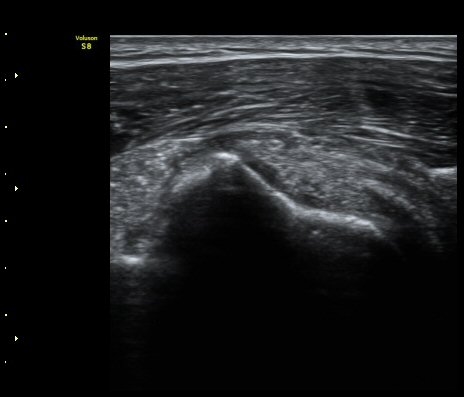

À̵ιڱ٠Ⱦ´Ü¸é°Ë»ç¿¡¼­ Á¡¾×³¶³» °í¿¡ÄÚ ¼®È¸È­ À½¿µµéÀÌ °üÂûµÊ(±×¸² 1, 2, 5)

À̵ιڱ٠Á¾´Ü¸é°Ë»ç¿¡¼­µµ Á¡¾×³¶³» ¼®È­È­ À½¿µÀÌ °üÂûµÊ(±×¸² 4).